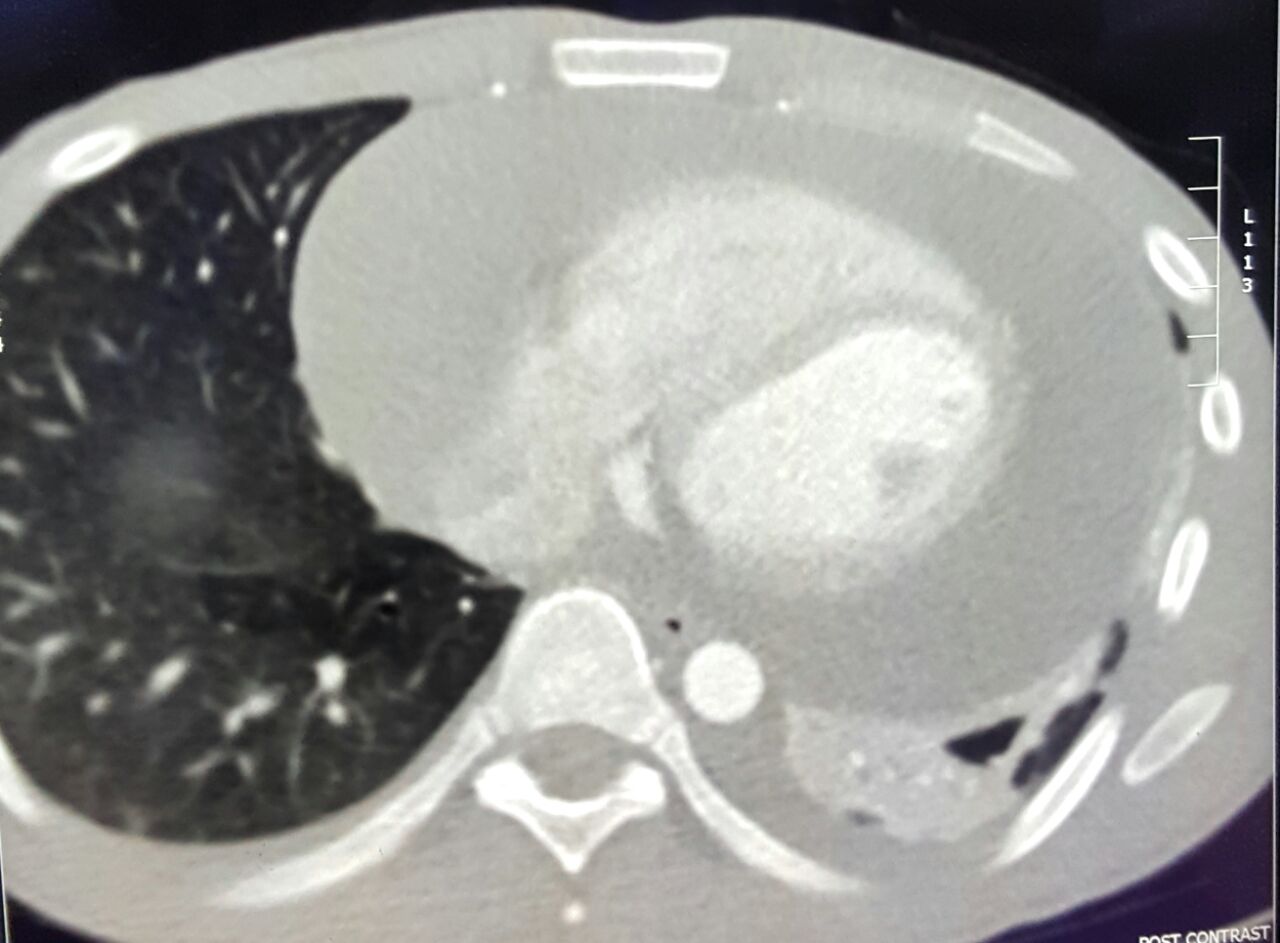

وقال استشاري جراحة المناظير والصدر بمستشفى الملك عبد العزيز التخصصي بالطائف، وعضو هيئة التدريس بكلية الطب بجامعة الطائف، الدكتور محمد عيد محفوظ، إن المريض أُدخِل من قبل الأخصائي المناوب بمجمع الملك فيصل بالطائف، وأودع العزل نتيجة الاشتباه بإصابته بفيروس كورونا، وأظهرت الفحوصات وجود تقيُّح شديد ومتعدّد بالصدر، مع التهاباتٍ والتصاقاتٍ شديدية بالرئة اليمنى، وضيقٍ بالتنفس، مع ارتفاعٍ بدرجة الحرارة، وأعراض تسمُّم بالدم.

وأضاف أنه تم التعامل فورًا مع الحالة، وخضع المريض لمنظارٍ جراحي متقدم عن طريق فتحتين تم من خلالهما تنظيف الصدر، وتحرير الرئة اليمنى من الالتصاقات وتجمّعات القيح حولها، وعمل الغسيل اللازم للصدر، مع وضع أنابيب تروية صدرية.